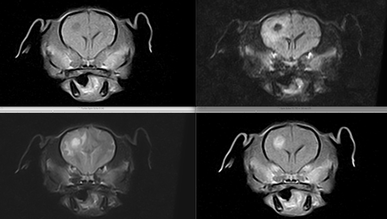

症例

13歳 猫

急性の斜頸とふらつき

MRI(左図)にて右中・内耳領域の高信号化あり

右側の中・内耳炎と診断

貯留液の採取および洗浄のために鼓室包切開術を実施

膿が採取されたため、薬剤感受性試験を行い抗生剤による治療を行い、その後症状良化

術前後のCT画像